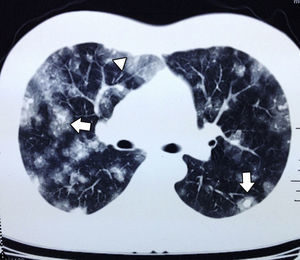

Se realizó autopsia, en la cual se observan tumoraciones redondeadas, vascularizadas en todo el injerto hepático, afectación a porta y arteria hepática (fig. 4), en parénquima pulmonar, múltiples metástasis las cuales forman lesiones pequeñas, con datos hemorrágicos (fig. 5). Además también presentaba metástasis en el bazo, glándulas suprarrenales y páncreas.

El angiosarcoma se presenta con metástasis tempranas a otros órganos como pulmón, bazo o hueso10. En las radiografías simples de tórax pueden encontrarse infiltrados difusos. Los hallazgos más comunes en la tomografía axial computada de tórax por metástasis de angiosarcoma son las lesiones múltiples sólidas, que cuando se presentan con hemorragia dan una imagen de vidrio despulido, que se conoce como signo del halo y ocurre en el 32% de los pacientes. En menor proporción pueden encontrarse cambios quísticos de paredes delgadas (13%) que cuando se distribuyen en las zonas pleurales aumentan la incidencia de neumotórax o hemotórax12.